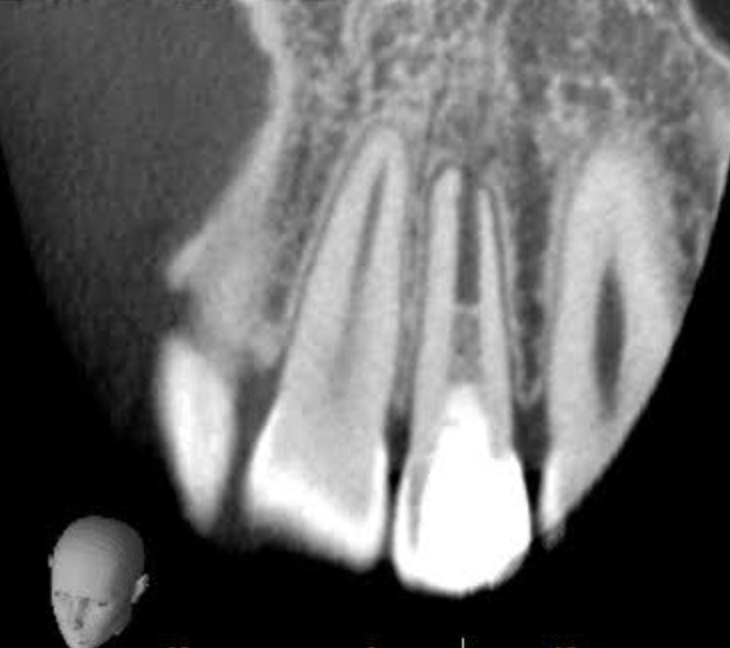

次の写真は根尖切除術後3ヶ月後で、根尖が順調に治癒し骨が再生してきています。

レントゲンやCTを用いて、膿の位置・広がり・骨の状態を正確に把握します。

炎症の程度により、治療計画や通院回数を決定します。